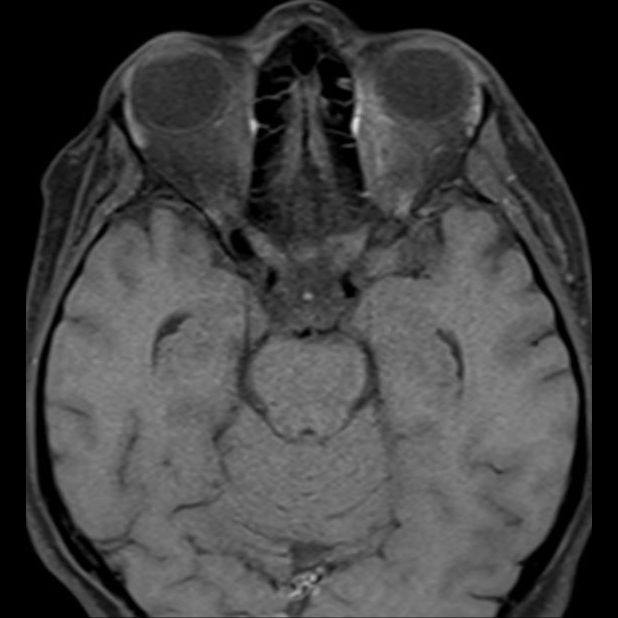

- (A) Torakal MRG’de sagital görüntülerde üst-orta torakal düzeyde T2A hiperintens (oklar), T1A izo-hipointens (ok) uzun segment ekspansil sinyal değişikliği izlenmekte olup sagital postkontrast T1A’da kontrast tutulumu mevcuttur (oklar). Bulgular longitudinal ekstensif transvers miyelit (LETM) ile uyumludur.

- (B) Orbita MRG’de aksiyel yağ baskılı T1A’da optik sinir prekiazmatik segmenti (oklar) gösterilmiş olup sırası ile aksiyel ve koronal post-kontrast yağ baskılı T1A görüntülerde bilateral optik sinir prekiazmatik segmentte kontrast tutulumu dikkati çekmektedir (oklar ve daire).

- Optik nörit varlığında özellikle optik kiazma ve posterior optik sinir tutulumu görülür ve bilateral olabilir.

- Transvers miyelit sıklıkla santral gri cevheri etkileyen ve üç veya daha fazla vertebral gövde uzunluğunu etkilemektedir (LETM).

- Kontrast madde enjeksiyonu sonrasında neredeyse tüm akut NMO lezyonları, yamalı, düzensiz veya periferik olarak kontrastlanma gösterir.